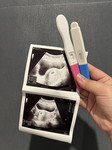

หาคุณหมอวันที่ 12 สิงหาคม 2568 อายุครรภ์ 9 + 2 weeks ขนาดตัวเจ้าจิ๋ว ประมาณ 3.09 เซนต์ ถือว่าผิดปกติ ไหมคะ

อายุครรภ์ 9+2 สัปดาห์ ขนาดตัว 3.09 ซม. ถือว่าอยู่ในเกณฑ์ปกติค่ะ